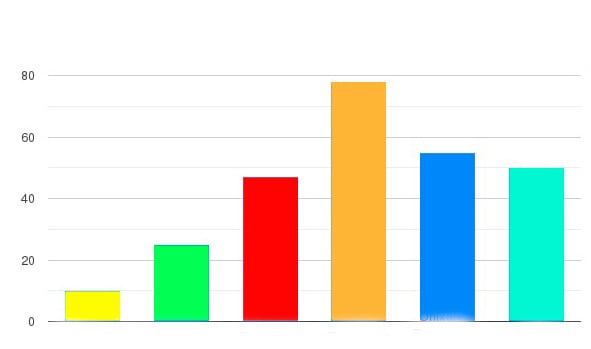

ეფექტურობა შესწავლილი და დადასტურებულია ჩვენს კვლევით ცენტრში. პროდუქტმა გაიარა მრავალი კლინიკური კვლევა მოხალისეებზე. შედეგები აჩვენებსClareon დადასტურებულ მაღალ ეფექტურობას:

- Excilor

- Yoffee Clear

- Spray Fungustan

- Onixan Premium

- Clareon

- Amorolfina Ratiopharm